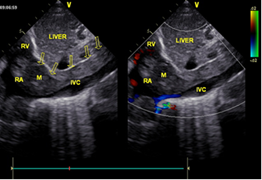

祁彦(化名)有子宫肌瘤病史,14年前在当地医院做过切除手术。一月前体检提示心脏肿瘤,B超提示:中下腹及盆腔内见巨大占位,与子宫关系密切,右侧髂内静脉经髂总静脉、下腔静脉延伸至右心房内可见中等低度回声,测右房内大小为34*51mm,心房内瘤体较大。

手术前后B超对比

12月4日,手术当日,妇产科陈必良教授、马佳佳医生开腹,游离出巨大的子宫肌瘤及双侧附件,切除后分离出瘤体远端,游离下腔静脉。心血管外科董小超副教授开胸在心脏不停跳并行体外循环下切开右房,探查右房内瘤体情况,通过腹部切口,将髂静脉切开分离肿瘤,于肿瘤起始部位切断肿瘤,自右心房内取出瘤体。循环稳定,术中食道超声持续观察以确定心内瘤体彻底取出。患者病变子宫极大,瘤体呈圆柱形,长约30-40cm。术后患者转入心血管外科监护室继续监护治疗。术后当天,患者恢复自主呼吸,生命体征平稳,顺利拔管。病情稳定后安返病房,与家人团聚。